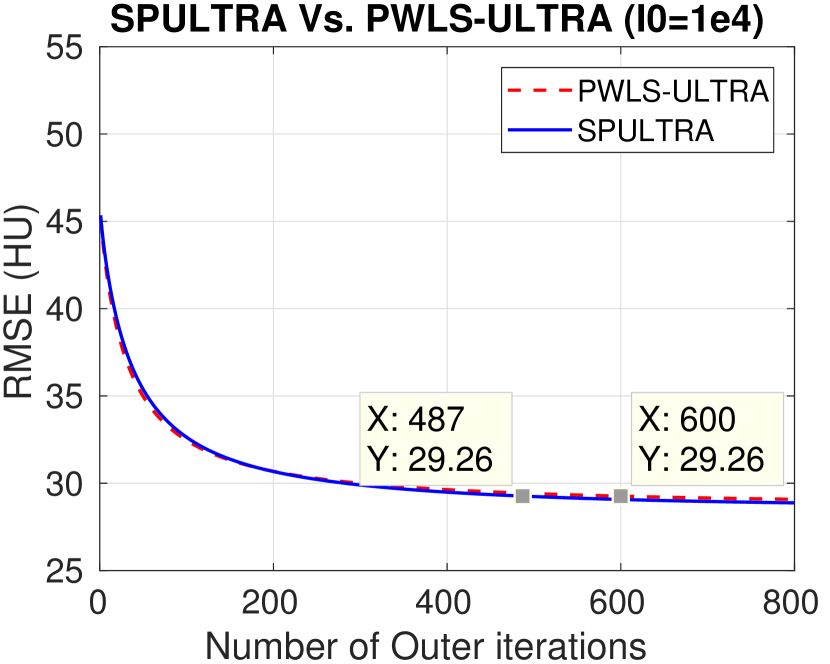

We compare the RMSE and the SSIM for SPULTRA with those for PWLS-EP and PWLS-ULTRA. Tab. II lists the two metrics for the reconstruction targeted ROI after sufficient iterations (800 iterations) for convergence of PWLS-EP, PWLS-ULTRA, and SPULTRA, for various dose levels. The results show that SPULTRA achieves significant improvements in RMSE and SSIM in low-dose situations. Notably, compared to PWLS-ULTRA, SPULTRA further decreases the RMSE by up to 1.3 HU when , and by around 3.3 HU when .

The RMSE improvement of SPULTRA over PWLS-ULTRA can be more clearly observed from Fig. 3 that shows the RMSE evolution with the number of outer iterations under different dose levels. At low-doses, SPULTRA decreases the RMSE more quickly (from the same initial value) and to much lower levels than PWLS-ULTRA. Fig. 3 shows that to achieve the same RMSE as PWLS-ULTRA at 600 outer iterations, SPULTRA takes 487, 365, 251 and 133 outer iterations under , respectively.

V-A4 Computational Costs

As discussed in Sec. III-D, SPULTRA has a similar computational cost per iteration as PWLS-ULTRA, except for computing some initializations for image update. Fig. 3 shows that the SPULTRA method requires much fewer number of outer iterations than PWLS-ULTRA to achieve the same RMSE for the reconstruction, especially at low doses.

When the dose is very low, e.g., when , SPULTRA takes only a quarter the number of outer iterations as PWLS-ULTRA to achieve the same RMSE. Thus, the total runtime to achieve a specific reconstruction quality at low doses is typically much lower for SPULTRA than for PWLS-ULTRA. When the dose is not very low, for example when , the SPULTRA and the PWLS-ULTRA methods have similar computational costs and runtimes. To achieve RMSE of 29.26 HU (see Fig. 3(a)), PWLS-ULTRA requires 600 outer iterations, while SPULTRA requires 487 584 effective outer iterations where the additional runtime is associated with initializations in each SPULTRA outer iteration.